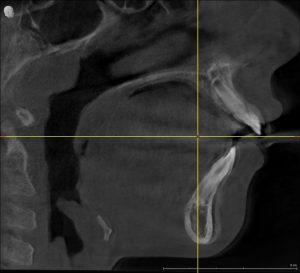

Diagnosis: More Than a Dental Problem

The child was diagnosed with:

- Upper airway constriction related to adenoid hypertrophy

- Maxillary transverse deficiency

- Mandibular retrusion

- Pediatric sleep-disordered breathing

This was not just an orthodontic issue — it was a growth, breathing, and sleep concern.